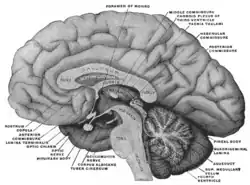

Blut-Hirn-Schranke

Als Blut-Hirn-Schranke, auch Blut-Gehirn-Schranke oder Blut-Hirn-Barriere genannt, wird die selektive physiologische Barriere zwischen den Flüssigkeitsräumen des Blutkreislaufs und dem Zentralnervensystem bezeichnet.

Anatomie der Blut-Hirn-Schranke